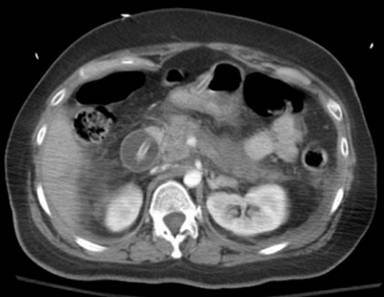

A 38-year-old white female with past medical history of mental retardation, seizure disorder, hypothyroidism and osteoporosis was admitted with complaints of painful abdominal distension, fever and vomiting. There was no history of prior alcohol abuse. Her medications included levothyroxine, phenytoin, docusate sodium and calcium carbonate. The patient was febrile (39.4 °C, 103 °F), hypotensive (87/49 mmHg) and tachycardic (122 min-1). On examination, the patient’s abdomen was distended, slightly firm with decreased bowel sounds but no guarding or rigidity. The hemoglobin was 17.3 g/dL, hematocrit 50.4% (reference range: 41.5-50.4%), white blood cells count 27,500 mm-3, and amylase 1,602 U/L and lipase 1,903 U/L, respectively. The liver enzyme tests, serum triglyceride level, serum calcium and IgG subclass 4 were normal. An ultrasound of the abdomen did not reveal any gallstone, sludge or biliary dilatation. A CT scan of the abdomen with oral and intravenous contrast showed peripancreatic fat stranding consistent with acute pancreatitis. A replacement gastrostomy tube balloon was noted to be impacted in the second part of the duodenum (Figure 2). The PEG tube was pulled back and secured to the abdominal wall. Aggressive hydration, ventilator support and antibiotics were administered. The patient’s clinical condition improved and the amylase and lipase returned to normal. The patient had no further episodes of pancreatitis.

Figure 2. CT scan of abdomen showing replacement gastrostomy tube balloon in the duodenum. Case #2. |